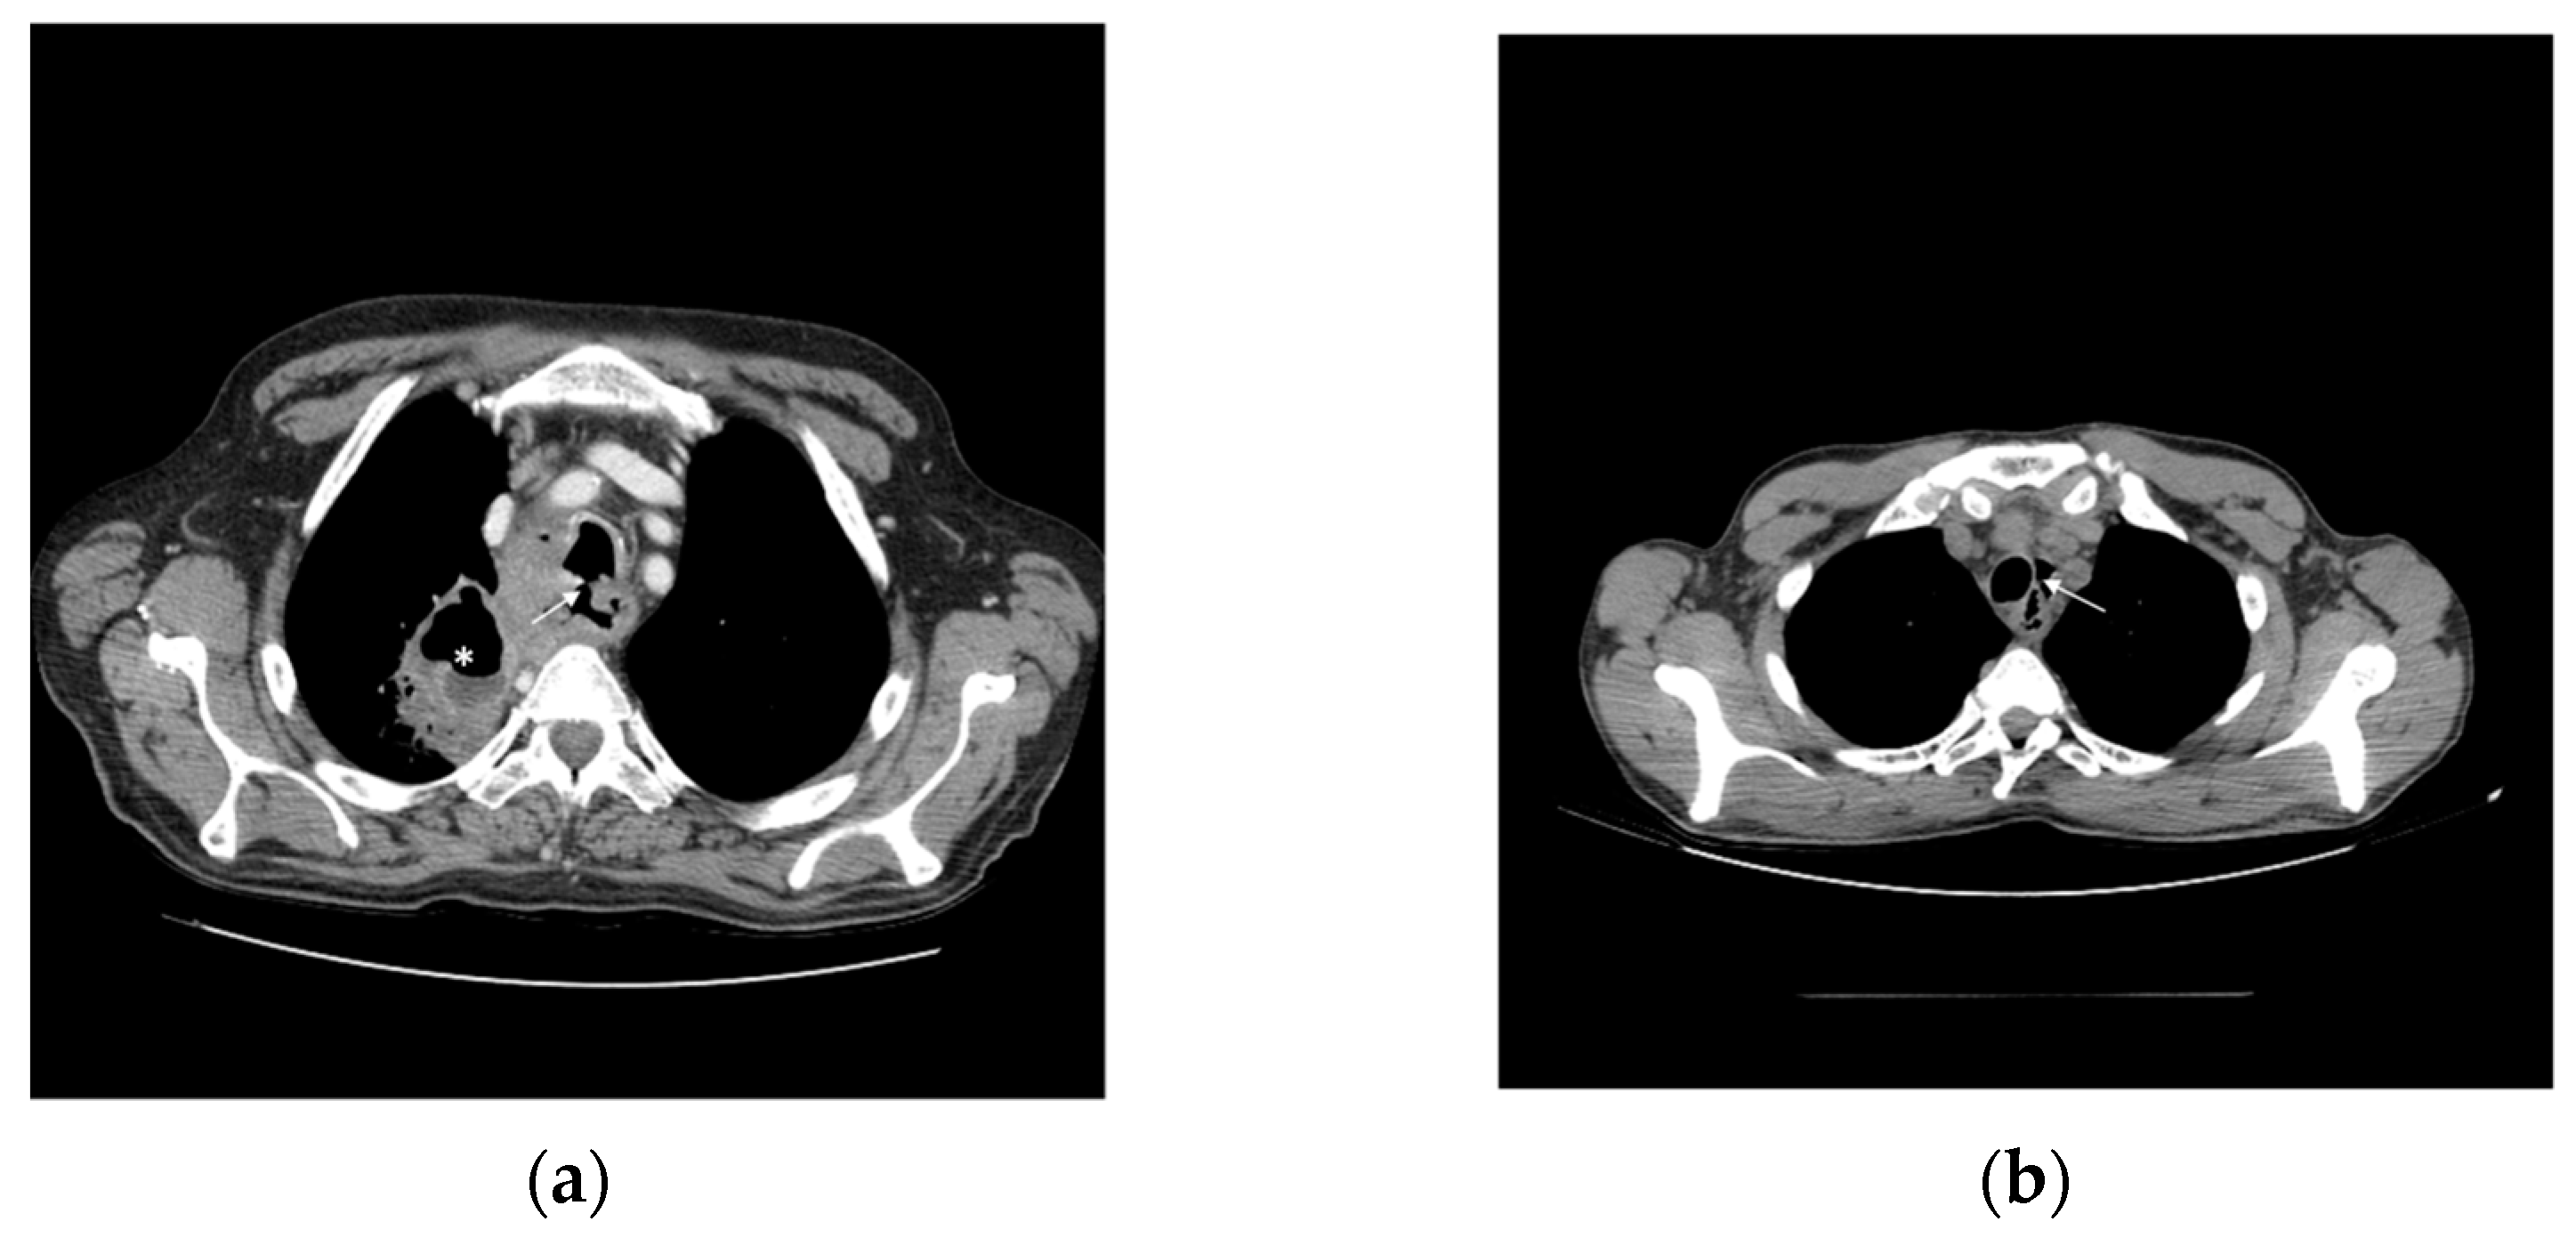

3.1.5. Fistula

- Di Mauro, P.; Ferrari, V. Bronchoesophageal Fistula. New Engl. J. Med. 2020, 383, e137. [Google Scholar] [CrossRef] [PubMed]

- Reed, M.F.; Mathisen, D.J. Tracheoesophageal fistula. Chest Surg. Clin. N. Am. 2003, 13, 271–289. [Google Scholar] [CrossRef] [PubMed]